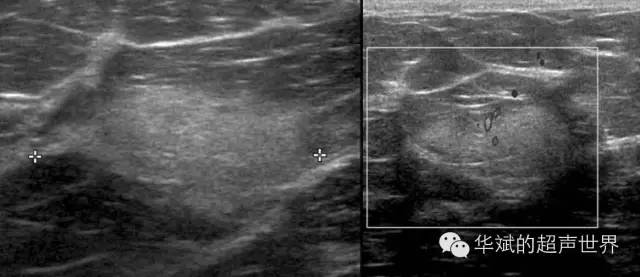

冬眠瘤(hibernoma),也叫蛰伏瘤、棕色脂肪瘤。是起源于棕色脂肪的一种良性肿瘤。发生在20-40岁的患者中,主要发生于肩胛间区和肩胛周围,也可以发生在其他部位。声像图上一般表现为高回声包块,边界不如单纯性脂肪瘤清晰,内部偶尔可见血流信号。

图3 乳腺内的冬眠瘤。